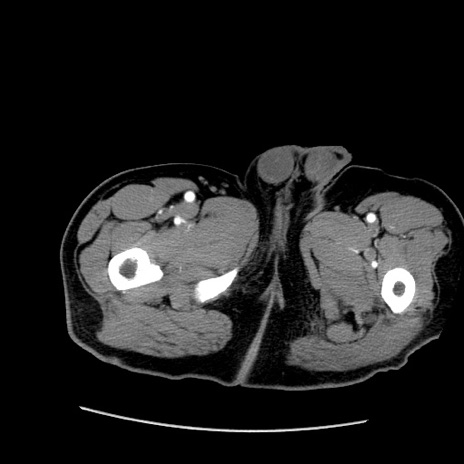

冠状断像

【症例】50歳代男性

【主訴】腹痛

【現病歴】AVMからの被殻出血のため回復期リハ病棟入院中。 本日午後3時頃急に下腹部痛が出現した。

【既往歴】AVM、被殻出血、虫垂炎、高血圧

【身体所見】意識晴明、左半身不全麻痺、会話の理解は良好、36.5°C、腹部:膨隆、全体に板状硬、下腹部正中に圧痛点あり、反跳痛-、筋性防御不明、右下腹部にope scar

【データ】WBC 9400、CRP 0.06